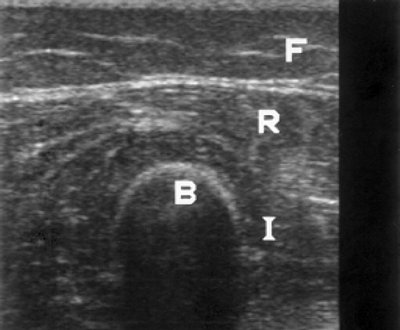

При обследовании мышц бедра четко дифференцировались прямая и широкие мышцы бедра, так как отделялись одни от других гиперэхогенными линейными структурами - фасциями. Все мышцы имели примерно одинаковую эхоструктуру; на гипоэхогенном фоне выделялись тонкие эхогенные полоски, расположенные в каждой мышце в определенном направлении, но обычно параллельные ее длинной оси и лучше видимые на продольных срезах. Происхождение этих сигналов связано с соединительно-тканными перимизиальными септами. На поперечных срезах мышцы имели округлый вид, так же как и их внутренние гиперэхогенные структуры. Эхогенность сокращенных мышц была несколько меньшей, чем у мышц, находящихся в состоянии расслабления. Кость на эхограммах, полученных на поперечных срезах, представлялась сильным дугообразным эхосигналом, сопровождавшимся "тенью", интенсивность которой прямо зависела от возраста пациента. Так, у пациентов младшего возраста ультразвук полностью не отражался от поверхности кости, что позволяло визуализировать ее полость. Внешний край мышц граничил с более эхогенным подкожно-жировым слоем, но в ряде случаев подкожный жир был сходен по плотности с мышцей, особенно у тучных пациентов (рис. 1).

а) Продольное сканирование.